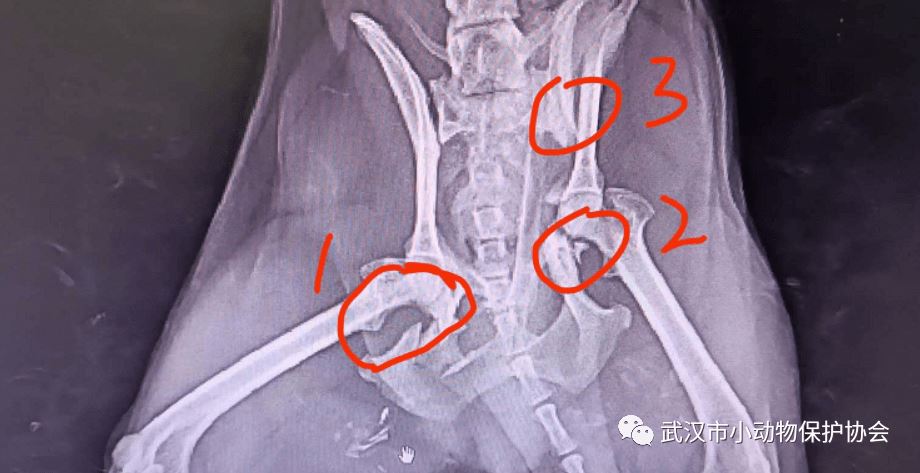

狗狗救助后带至动物医院拍片检查,发现确为车辆碾压导致的骨盆三处骨折(还有双侧隐睾),住院观察一段时间,择期手术。

动物信息:田园犬(比熊串)姓别:公年龄:约2 岁 取名:金城

金城的医疗费是4300元